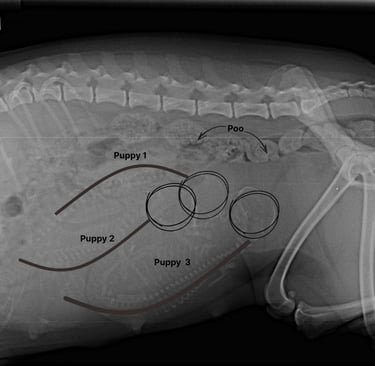

The atmosphere is carefully curated: her nest ready, blankets fluffed, room temperature kept steady, and the background tuned to “serene spa” rather than household chaos. She’s had a sanitary groom to keep her comfortable and clean, and X‑rays revealed the little lineup waiting inside—puppies poised for their grand debut, each one a secret still tucked beneath her rounded belly.

Inside the uterus, positioning becomes critical. As you can see in the x-ray, the puppies have rotated into a head‑down orientation, aligning themselves for the birth canal like actors waiting in the wings for their cue. The uterine environment is now crowded, each pup pressed against its siblings, yet still undergoing a rapid growth spurt as fat deposits accumulate to regulate body temperature after birth. Their coats are fully grown, complete with markings that will distinguish each one, and their nervous systems are firing in preparation for the sensory flood of the outside world.

Poppets X-ray. Day 56/63